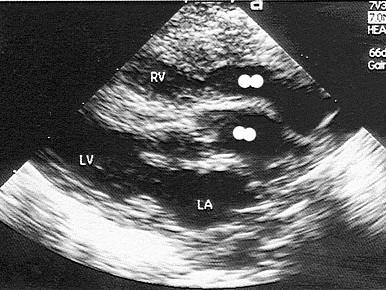

该病例最可能的诊断?(?)A.矫正型大动脉转位B.右室双出口C.完全性大动脉转位D.主动脉骑跨E.单心室

选项 A.矫正型大动脉转位 B.右室双出口 C.完全性大动脉转位 D.主动脉骑跨 E.单心室

答案 C